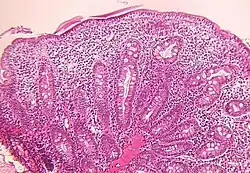

Small bowel

Microscopic examination of a biopsy of the small bowel in these patients shows villous atrophy with low or no mononuclear cell infiltration of the lamina propria nor specific abnormalities involving the epithelium. The amount of villous atrophy does not explain the severity of the diarrhea.

Studies of enterocyte brush-border ion transporter proteins (sodium-hydrogen exchanger 2, sodium-hydrogen exchanger 3, aquaporin 7, sodium-iodide symporter and hydrogen potassium ATPase) showed reduced expression or mislocalization in all patients with different profiles for each.[6]